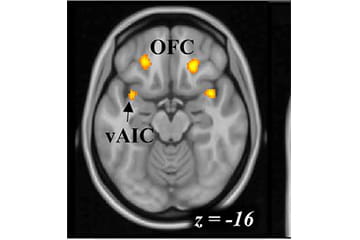

image of a brain scan

fMRI Study of Working for Alcohol

In addition to an in-person screening, this study requires an overnight stay at University Hospital’s Clinical Research Center in Indianapolis. On the first day, participants briefly experience intravenously administered alcohol and have an MRI at Goodman Hall while they perform a task. Depending on task performance, participants may then have the opportunity to administer themselves intravenous alcohol following the MRI scan. Participants then spend the night at University Hospital and are discharged at 10:30 am the following day. This study is conducted primarily on Tuesdays, Wednesdays and Thursdays. Participants in this study receive up to $575 and have the opportunity for additional payment during the study visit.